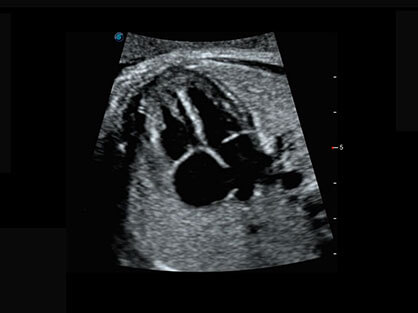

通过对组织运动信息、血流信号及背景噪声进行准确智能的阈值判定,高效提取出微弱血流信号,获得高灵敏度和空间分辨率的血流图像,为临床提供更加真实和丰富的诊断信息。

宽频带腹部凸阵探头和腹部容积探头、大角度腔内探头和腔内容积探头、独特的生殖专用曲柄探头,为妇产应用提供全面诊疗方案。

卵泡结构的自动识别和测量,可显示多组测量数据。